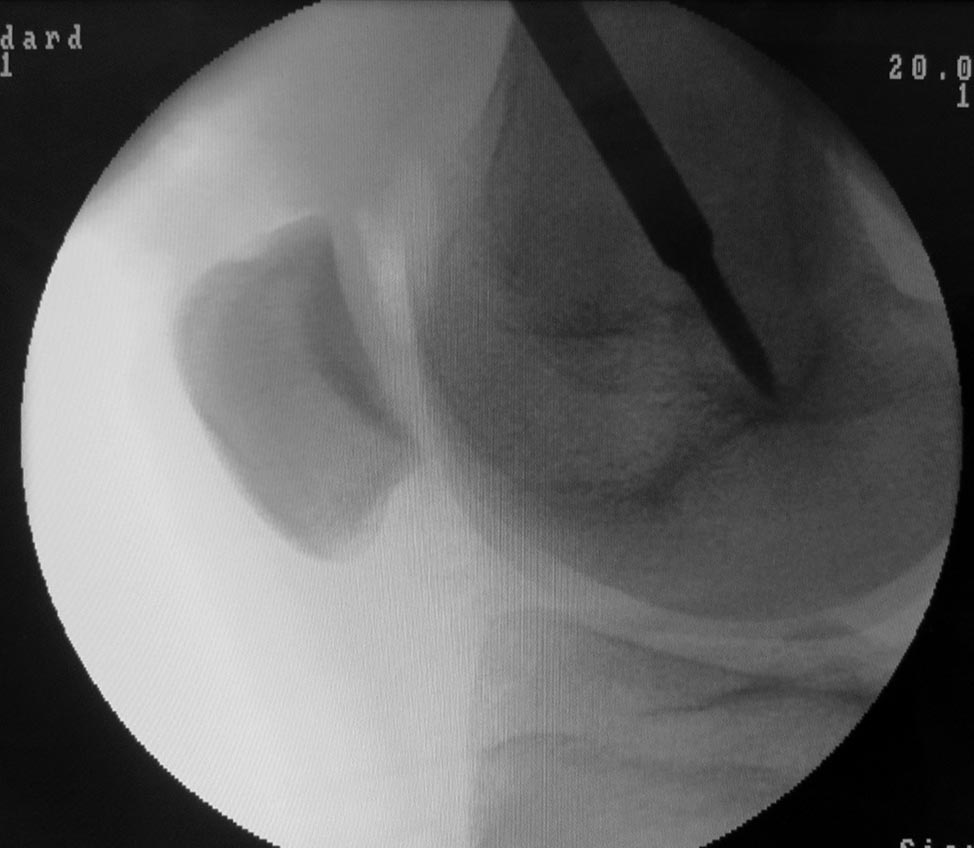

Se toma un injerto del tendón cuadricipital (TC) de espesor completo dejando un margen de 2-3 mm en la zona medial, para permitir un cierre del defecto tendón-tendón. Es importante evitar abrir la cápsula articular. Para ello es conveniente comenzar la disección aproximadamente 3 cm proximal al polo superior de la rótula donde el tendón se encuentra bien diferenciado de la cápsula articular, y luego continuar hacia proximal (Fig. 3). Finalmente se continúa hacia distal con una disección subperióstica hasta la inserción anatómica del LPFM en la rótula. Este gesto permite ganar 1-1.5 cm de longitud final del injerto. Se mantiene la inserción rotuliana del TC y se lo gira sobre sí mismo de modo que la cara posterior quede anterior y viceversa. Se fija el extremo distal del tendón con puntos tipo Krakow y se refuerza la inserción rotuliana con puntos en 8, ambos con suturas no absorbibles tipo Fiberwire. Se diseca el plano entre vasto medial oblicuo (VMO) y el retináculo medial. Se identifica con el arco en C, en un perfil estricto, el punto anatómico de inserción femoral del LPFM. Este paso es crítico al momento de la reconstrucción. En pacientes esqueléticamente maduros utilizamos el punto de referencia radiográfico descripto por Schöttle.7 En pacientes esqueléticamente inmaduros fijamos el injerto en la región epifisaria inmediatamente distal al cartílago de crecimiento (Fig. 4), ya que este punto de referencia no es fiable en pacientes con fisis abierta.8

Figura 4: Imagen de frente y perfil donde se identifica el punto de inserción femoral con arco en C en un paciente esqueléticamente inmaduro. Nótese la posición inmediatamente distal a la fisis en el frente y alineada con la cortical posterior del fémur en el perfil